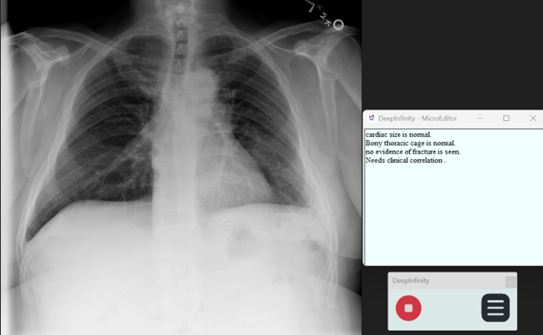

Step 15: Micro Editor for instant reporting

Click on the Menu button and click on Micro editor button to open micro editor Micro Editor

Sample Report Using Micro Editor

Micro Editor Sample Report